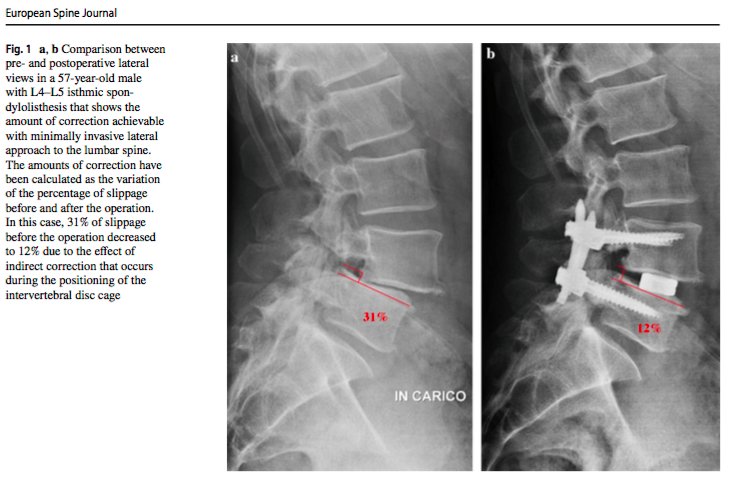

Check this article about

#minimally invasive surgery procedure in isthmic#spondylolisthesis http://goo.gl/wLzXof pic.twitter.com/lL10KWL2xu